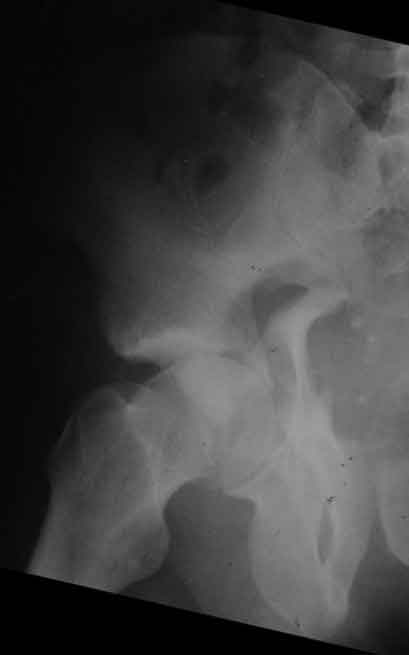

Дополнение, минимальный набор необходимых прекций, необходимых для лечения повреждений вертлужной впадины

Подвздошная Запирательная